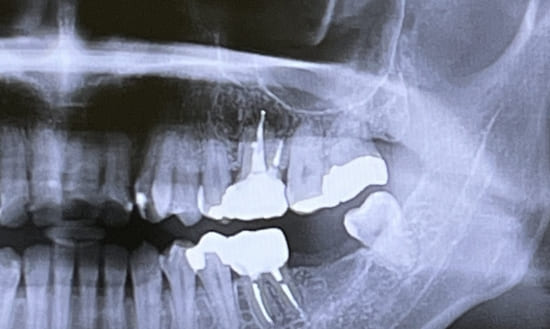

• 02 検査

レントゲン写真を撮影して、それを元に治療の計画を立てていきます。必要に応じて歯科用CT撮影も行いますが、撮影は提携しているCTセンターにて行っていただきます。

レントゲン写真やCT撮影をもとに、患者様に適した治療方法をご提案させていただきます。